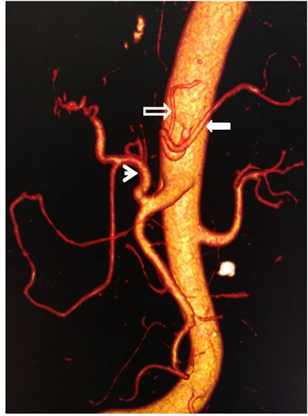

One hundred and twenty-eight patients (80%) had a classical anatomical configuration of celiac trunk, while thirty-two (20%) had at least one AV. Two AVs were found in 15 patients (9.4%) while five other patients (3.1%) had more than two AVs. Bifurcation of celiac trunk was the most common type of AV with a total of 14 patients, including hepato-splenic bifurcation (Figure 2), with 12 patients (7.5%). The second type of bifurcation found was gastro-splenic with 1.3% (Figure 3). Collateral arteries were the second most frequent type of AVs with a

Figure 3. Enhanced abdominal CT-scan showing on 3D reconstruction, a gastro-splenic bifurcation with a stomachic coronary artery (hollow arrow), a splenic artery (full arrow) and a common hepatic artery (arrow head).

total of 9 patients or 5.6%. Of these, left hepatic artery (Figure 4) and lower right diaphragmatic artery were the most common with three patients each. Then common celiac and mesenteric trunk followed (Figure 5) with 5 patients.